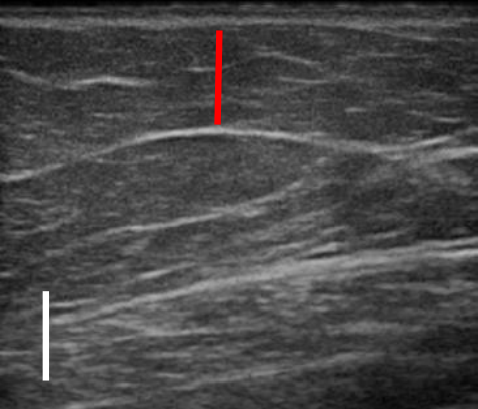

트루스컬프iD 시술 전 / 12주 후 초음파 사진 비교

트루스컬프 아이디 시술 전, 12주 후 초음파를 비교한 사진입니다.

앞서 보았던 뱃살 사례보다 눈에 띄는 변화는 없었으나 실제로 감소한 지방량이 상당했는데요. 시술 전과 비교했을 때 약 31% 정도 지방이 감소했습니다.

뱃살, 옆구리살이 너무 많은 경우 실제 눈에 보이는 것보다 내부에 쌓여있는 지방이 두터운 경우가 많아 시술을 해도 큰 변화를 보이지 않는 경우가 많은데요. 실제로 시술 후 큰 변화가 없어 실망하는 분들도 많지만 위와 같이 초음파 검사를 통해 속을 들여다보면 상당 부분 지방이 감소한 것을 확인할 수 있습니다.